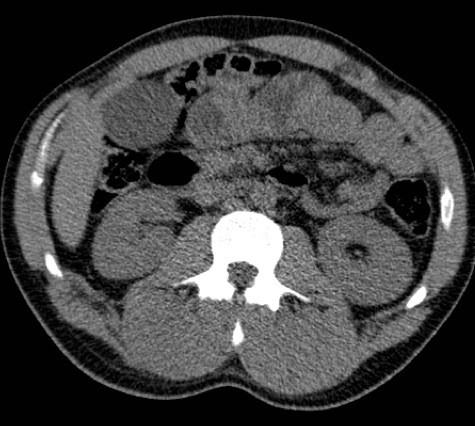

Acute bilateral paraspinal compartment syndrome

Patient is a bit of a gym junkie and did a particularly strenuous session prior to the onset of symptoms. Patient had hematuria with 2 days of severe low back pain radiating into the groin and right leg. Khan et al. Acute paraspinal compartment syndrome. A case report. J Bone Joint Surg Am. 2005 May; 87(5):1126-8.

Courtesy Bill Breidahl, MD